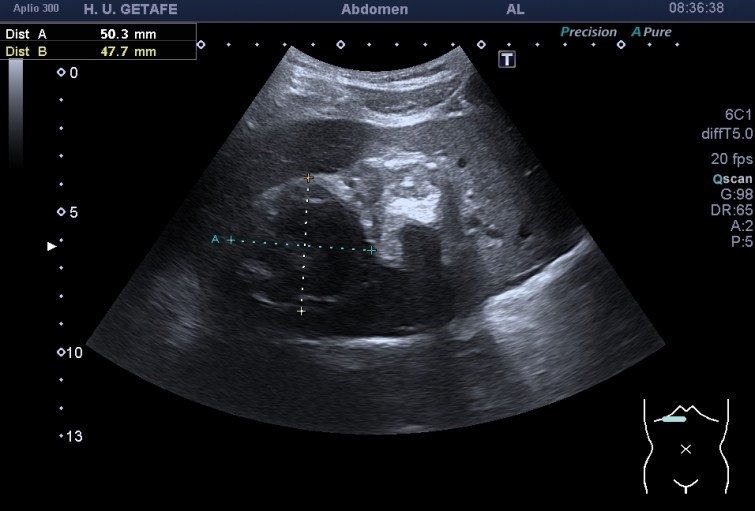

Durante la exploración de una eco de abdomen en el contexto de un paciente que acude por elevación de transaminasas observo una imagen heterogénea, irregular, con una pared marcadamente calcificada, bilobulada de gran tamaño que medí en dos partes ya que me pareció claramente que estaban diferenciadas.

Una de ellas, la primera, era mucho más hiperecogénica y más pequeña, su centro estaba mas calcificado, su sombra acústica posterior era mucho más acuciada y llamaba más la atención. Justo al lado, otra lesión de mayor tamaño, su calcificación era mucho más sutil y más periférica delimitando una LOE hipoecogénica de un tamaño muy importante, adyacente a la más pequeña, como he comentado previamente. Ambas sin señal Doppler.